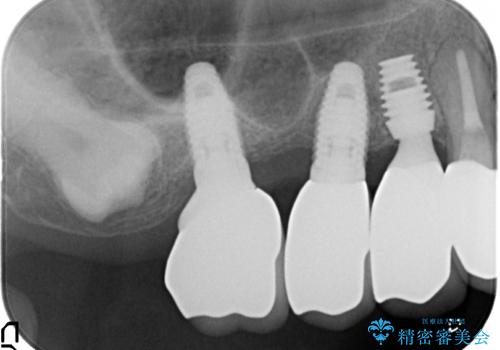

薄い骨にもインプラントを スプリットクレスト+ショートインプラントの応用

- 破折により保存不可能となった歯を抜歯後、待時してインプラントを計画した。

骨が薄く、インプラントの径に耐え得ないと判断したためスプリットクレストにより骨幅を拡大しインプラントを埋入した。

スプリットクレストやリッジエキスパンジョンといった方法は、骨が薄く、細い場合に、割線を設定し、狭い骨幅を拡大すると同時にインプラントを埋入することができます。

インプラントの種類:Bicon

かぶせ物の種類:PFZ